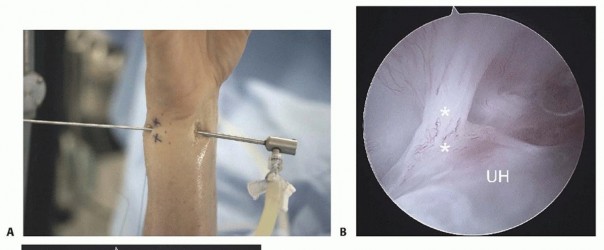

The volar DRUJ portal is accessed through the volar ulnar skin incision ( TECH FIG 7A-E).The joint is entered by angling the 22-gauge needle 45 degrees proximally.It is useful to leave a needle or cannula in the ulnocarpal joint for reference.Alternatively, a probe can be placed in the distal DRUJ portal and advanced through the palmar incision to act as a switching stick over which the cannula can be threaded. 5Initially, the space appears quite limited, but over the course of 3 to 5 minutes, the fluid irrigation expands the joint space, which improves visibility.A 3-mm hook probe is inserted through the dorsal distal DRUJ portal for palpation.A burr or thermal probe can be substituted as necessary.Direct visualization of the foveal attachment prevents accidental injury to this structure. The articular disc is seen superiorly.Proximal surface tears of the TFCC, which are usually caused by severe axial load, may be detected through this portal.The dome of the ulnar head lies inferiorly.The TFCC attachment to the sigmoid notch can be palpated with a hook probe in the distal dorsal DRUJ portal as it penetrates the dorsal DRUJ capsule.The deep attachments of the dorsal radioulnar ligament can be seen as it inserts into the fovea.In ideal cases, the conjoined tendon of the dorsal radioulnar ligament, ulnar collateral ligament, and palmar radioulnar ligament can be visualized.

DORSAL DISTAL RADIOULNAR JOINT PORTAL

TECH FIG 7 •(continued)D. View of a radial TFC tear from the 4-5 portal under dry arthroscopy. Note the exposure of the ulnar head (arrow).TFCC, triangular fibrocartilage complex. E. View of the same TFC tear from the VDRU.UH, ulnar head.The joint space is entered by inserting a 22-gauge needle horizontally at the neck of the distal ulna.Fluoroscopy facilitates needle placement.The distal dorsal DRUJ portal is identified 6 to 8 mm distally with the 22-gauge needle and just proximal to the 6R portal.This portal can be used for outflow drainage or for instrumentation.It lies on top of the ulnar head but underneath the TFCC and so is difficult to use in the presence of positive ulnar variance.The TFCC has the least tension in neutral rotation of the forearm, which is the optimal position for visualizing the articular dome of the ulnar head, the undersurface of the TFCC, and the proximal radioulnar ligament from its attachment to the sigmoid notch to its insertion into the fovea of the ulna.Because of the dorsal entry of the arthroscope, the course of the dorsal radioulnar ligament is not visible until its attachment into the fovea is encountered.Entry into this portal provides views of the proximal sigmoid notch cartilage and the articular surface of the neck of the ulna.